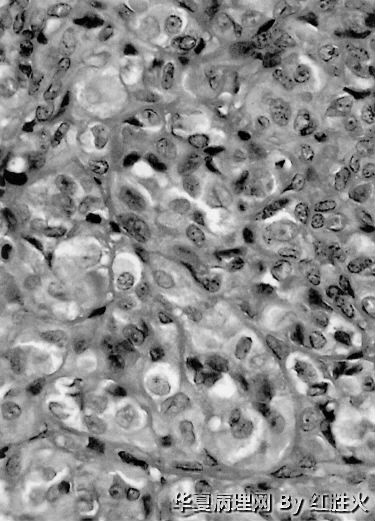

本例具有部分经典神经鞘瘤的形态特点,如有细胞密集区和疏松黏液样区、血管壁透明变性;又有其特殊形态,既可见菊形团样结构。因而争论的焦点在于是上皮样神经鞘瘤不是神经母细胞瘤样神经鞘瘤,这两种神经鞘瘤的亚型分别于1998和1994年见于文献报道,本例虽有菊形团样结构,但菊形团较小不够突出,另外其瘤细胞胞质较为丰富呈上皮样(神经纤维瘤样神经鞘瘤的瘤细胞缺少胞质),HE形态诊断上皮样神经鞘瘤更为客观,加做Ⅳ型胶原如能显示瘤细胞周围的基底膜样物质,则可进一步证实。

3、高倍镜下观察到以下特点:(1)中等大小的血管呈管壁玻璃样变性;(2)细胞核有深染、不规则形,但罕见核分裂,类似于退变性核;(3)细胞呈卵圆形、圆形或多角形,粘液样变区可见细胞界限较清,排列方式巢、索状,细胞浆较丰富,红染;(4)可见纤维性中心的菊形团样结构。